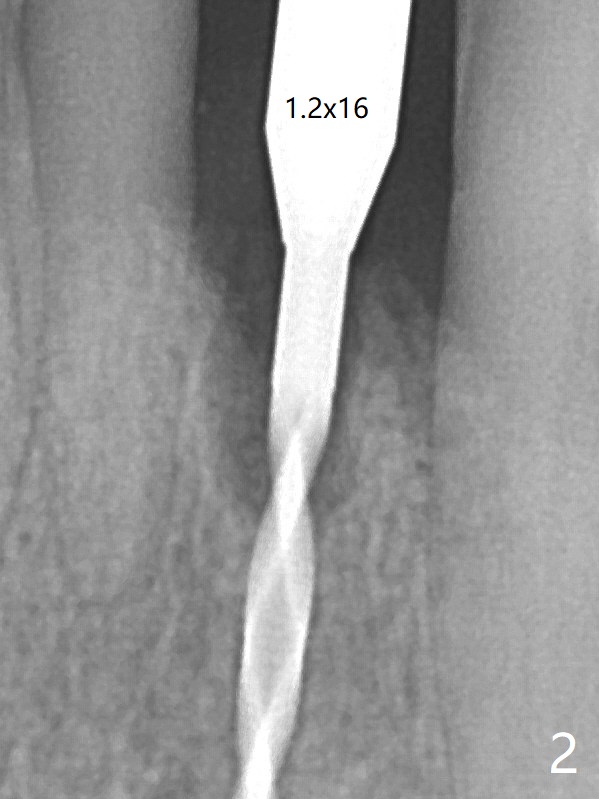

The gingival depth is measured 2-4 mm after extraction. The 1st intraop PA taken with 1.2 mm drill for 16 mm shows the mesiodistal width is 5.11 mm (Fig.2); a 2.5x14(2) mm 1-piece implant is placed with >35 Ncm (Fig.3 with allograft placed). There is no bone loss 3 months postop (Fig.5). The distal crest seems to be reduced in density and lower in height 1 year 7 months (Fig.7) and 1 year 11 months (Fig.8) post cementation. The severity does not worsen probably related to use of water pik.